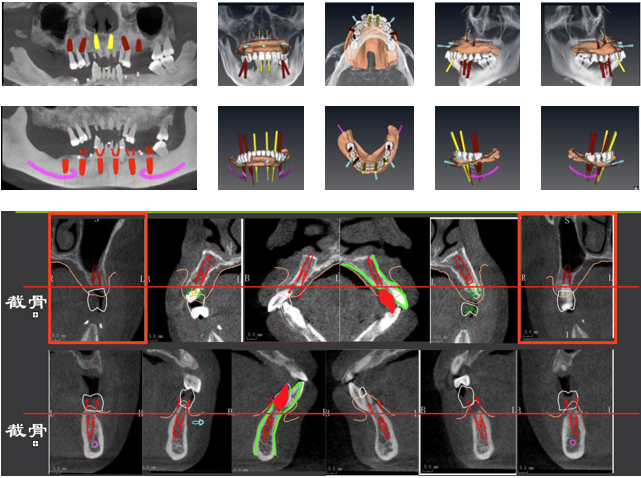

· 上下颌计划各植入六颗straumann钛锆种植体行即刻种植即刻修复。

2) 种植外科的难点:种植位点的设计,重度牙周炎患者如何在即刻种植即刻修复中应用数字化导板以及术中如何精确去骨;

· 制作放射导板,进行数字化导板设计。

· 上下各计划植入6颗种植体。其中14、24种植体倾斜植入,15、25经牙槽嵴顶上颌窦提升植骨,其余牙位无需植骨。

种植体位置设计,可见上前牙唇侧骨量过丰满,需适量去骨。同时上下颌均需要截骨处理。

· 上下颌士卓曼360数字化导板 +预成临时修复体设计图。

· 士卓曼360导板包括:骨支持的基部导板 、牙支持的辅助导板 、就位于基部导板的种植导板 以及就位于基部导板的预成临时修复体组成。

· 上下颌计划行即刻种植,各植入六颗straumann钛锆种植体并行即刻修复。